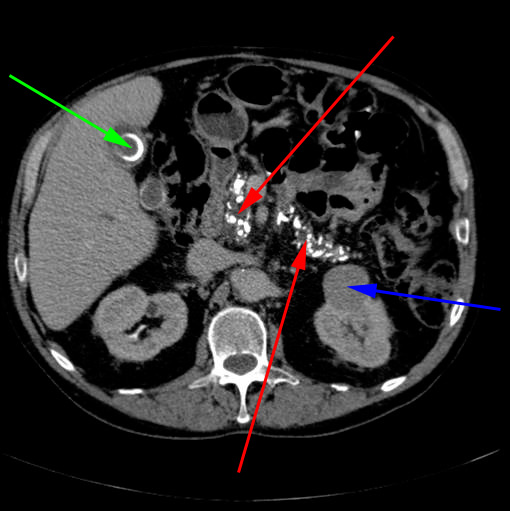

CT-skanning af øvre abdomen. Der er kalkudfældninger i bugspytkirtlen (røde pile), hvilket skyldes en kronisk betændelsestilstand i kirtlen (kronisk pankreatitis). Der er en cyste i venstre nyre (blå pil) og en stor galdesten (grøn pil) i galdeblæren.